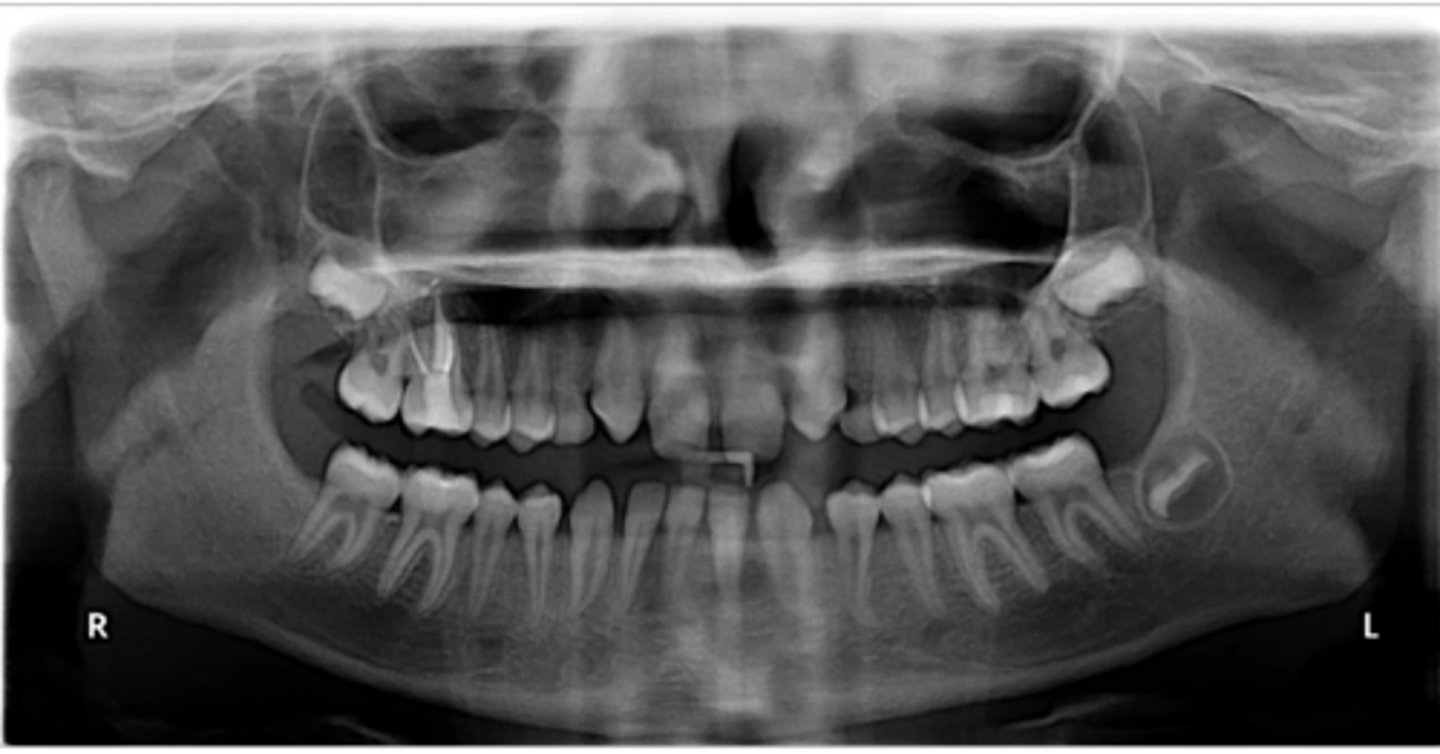

Class II skeletal (very light)

What type of skeletal malocclusion is this patient?

Hypodivergent

Are the hyper-, hypo-, o normo- divergent?

proclined

Maxillary incisors are?

Class II

Hyperdivergent

Class I

Normodivergent

No

Are the maxillary incisors proclined/flared?